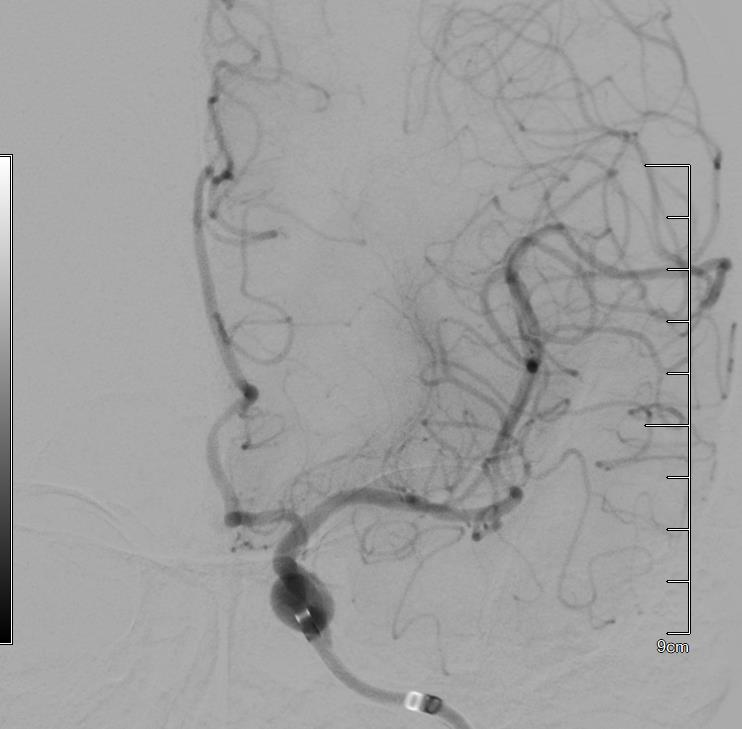

患者术后血管再通

术中,专家团队沉着应战、精准操作,凭借过硬技术与默契配合,从穿刺到血管成功再通仅用时11分钟,以“极速救治”完成了这场与死神的赛跑。术后,在医务人员密切监护和精心照料下,患者可基本独立下床活动,预后效果较好,悬在家属心中的“石头”终于落地。